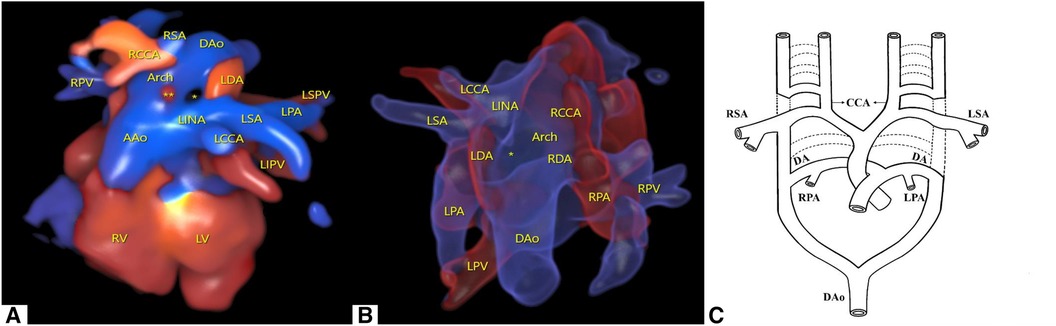

The embryological mechanism of development of the aortic arch has always been supported by Edward's theory, namely, the double aortic arch system (3). The value of this theory lies in its ability to explain the potential contribution of almost all embryonic arches to the final adult arch system components (1). As shown in Figure 3A, this is a complex process of development and regression. The primitive aorta is composed of ventral and dorsal parts. Six pairs of primitive arch arteries develop between the ventral and dorsal aortae. The dorsal aortae also give rise to the seventh intersegmental arteries. The appearance and degeneration of the primitive arch artery do not occur simultaneously. Ultimately, the first, second, and fifth pairs of primitive arch arteries degenerate. In normal development, the right proximal sixth arch continues to exist as the proximal part of the RPA, while its distal part degenerates as the DA, in addition to partial degeneration of the right dorsal aorta (dotted line in Figure 3A). The primitive third, fourth, and sixth pairs of arch arteries contribute to the common carotid artery, future aortic arch, proximal pulmonary artery, and DA, respectively. The seventh intersegmental arteries contribute to the subclavian artery (black solid line in Figure 3A) (1, 4, 5).

Figure 3. Edward's DAA system theory and the nine combinations of BDA and aortic arch abnormalities summarized in the literature. (A) Edward's DAA system theory. The dotted line represents regression, and the black solid line represents the preserved primitive arch artery. Reprinted with permission of Radiological Society of North America, from Hanneman et al. (1). (B) RAA combined with an ILSA. The LSA originates from the LPA via the LDA. (C) RAA-MIB combined with PA. The LPA originates from the LSA via the LDA. (D) RAA-MIB with or without PA. The LPA originates from the LINA via the LDA. (E) RAA combined with an aberrant left subclavian artery (ALSA). The LDA is connected to the LPA and ALSA. (B–E) RDA is connected to the RPA and the DAo. (F) DAA combined with BDA. The LDA is connected to the LPA and left arch, and the RDA is connected to the RPA and right arch. *represents interruption of the aortic arch (IAA) occurring in the right arch; **represents IAA occurring on both sides of the aortic arch. (G) LAA combined with IRSA. The RSA originates from the RPA via the RDA. *represents IAA occurring in the left arch. (H) LAA, RPA originates from the RSA via the RDA, with or without PA. *represents IAA occurring in the left arch. (I) LAA, RPA originates from the INA via the RDA, with or without PA. (J) LAA combined with ARSA, with or without PA. The RDA is connected to RPA and ARSA, respectively. (G–J) LDA is connected to the LPA and the DAo. The shadowed area in panels (C–E) and (H–J) represents PA.

In the present case, both primitive sixth arches had not degenerated. The partial degeneration of the left dorsal aorta occurs near the sixth and fourth arch arteries; that is, degeneration of the left aortic arch occurs between the LSA and LDA. Therefore, it causes the RDA and LDA to be directly connected to DAo (Figure 2C). The degeneration of different combinations of the primitive fourth and sixth arch arteries can lead to different types of aortic arch and DA.

We have summarized the nine combinations of BDA and aortic arch, which mainly include the right aortic arch (RAA), double aortic arch (DAA), and left aortic arch (LAA), and classified the combinations into three types. Type I refers to the RDA of the RAA connected to the RPA and DAo, with the LDA being ectopic. Type II refers to the LDA of the LAA connected to the LPA and DAo, with the RDA being ectopic. Type III refers to the bilateral DA connected to the aortic arch or near the DAo, with the other end connected to the pulmonary artery. Under each type, subtypes were classified as follows: a is the aortic branch, which is not connected to the aortic circulatory system originating from the pulmonary circulatory system via the DA; b refers to the pulmonary artery branches originating from the aortic circulatory system via the DA; and c usually occurs when the pulmonary artery is connected to the aberrant subclavian artery via the DA.

We refer to Type Ia, named isolated left subclavian artery (ILSA), as LPA-LDA-ILSA (Figure 3B) (6–9). Type Ib1 is characterized when the RAA-MIB is combined with PA, and the LPA originates directly from the LSA via the LDA; we refer to it as LPA-LDA-LSA (Figure 3C) (10). Type Ib2 occurs when RAA-MIB is present with or without PA, and the LPA originates from the LINA via the LDA; we refer to it as LPA-LDA-LINA (Figure 3D) (13–16). Type Ic occurs when the LDA is connected to the LPA and the aberrant LSA (ALSA); we refer to it as LPA-LDA-ALSA (Figure 3E) (10, 14, 17–19). In type I, the RDA mentioned above are all connected to the RPA and Dao; we refer to it as RPA-RDA-DAo.

We refer to Type IIa, named isolated right subclavian artery (IRSA), as RPA-RDA-IRSA (Figure 3G) (23–26). In Type IIb1, the RPA originates directly from the RSA via the RDA, with or without PA; we refer to it as RPA-RDA- RSA (Figure 3H) (10, 27). In Type IIb2, the RPA originates from the INA via the RDA, with or without PA; we refer to it as RPA-RDA-INA (Figure 3I) (9, 10, 14, 15, 28–30). In Type IIc, the RDA is connected to the RPA and aberrant RSA (ARSA), with or without PA; we refer to it as RPA-RDA-ARSA (Figure 3J) (10). In Type II, the LDA mentioned above are all connected to the LPA and Dao; we refer to it as LPA-LDA-DAo.

In Type III, we summarized two situations. The first one is our case, which involves an RAA with a bilateral DA connected to the Dao; we refer to it as LPA-LDA-DAo and RPA-RDA-DAo. Another type is DAA, where the LDA is connected to the LPA and LAA and the RDA is connected to the RPA and RAA; we refer to it as LPA-LDA-LAA and RPA-RDA-RAA (Figure 3F). The combination of DAA and BDA is very rare (20). In addition, two cases were found with this combination, one with interruption of the aortic arch (IAA) on the right side (21) and the other with a double side (22).

Coincidentally, Ia and IIa, Ib and IIb, and Ic and IIc almost form a mirror effect (Figures 3B and G, C and H, D and I, and E and J), which helps us to better understand and remember these patterns. In most cases, ectopia is always on one side of the BDA, almost occurring on the opposite side of the aortic arch, which seems to have some potential association. If there is PA, the blood supply to the pulmonary artery branch by the aorta is via the DA. At this point, the DA is defined as an abnormal connection rather than an ectopic connection. In our case, it is rare for the BDA to directly connect to the DAo without an ectopic connection, as we emphasized earlier.